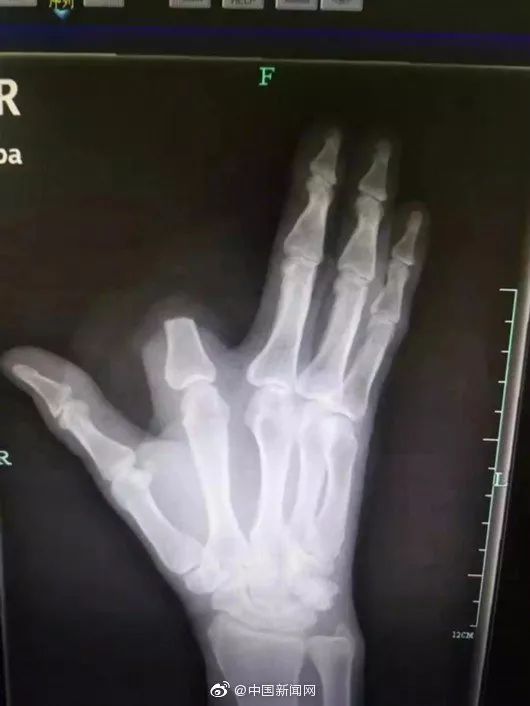

竟斩断手指自救…

医生说,完全没必要。

图片来源:杭州日报

目测,

是武侠小说看多了…